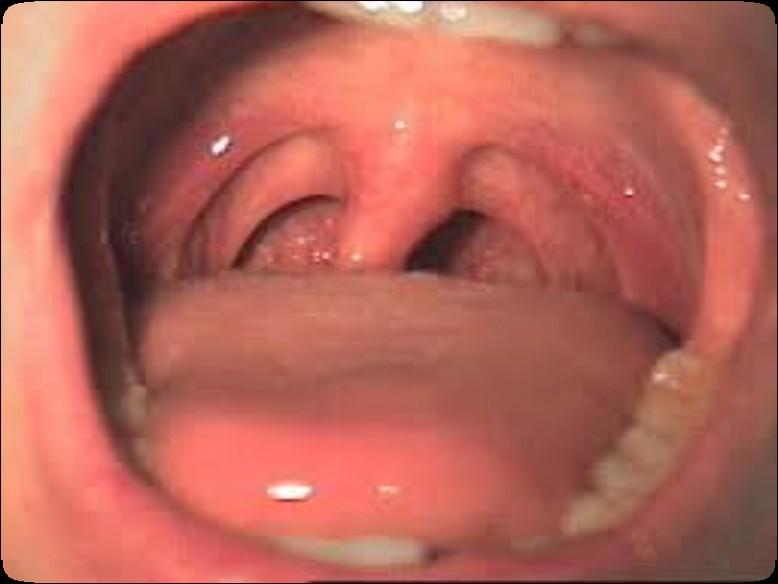

The Orofacial Complex

Dentition (teeth)

Periodontium (gums and bone)

Mucosa (soft tissue)

TMJ & Masticatory System (joint and chewing)

Salivary Glands & Saliva (spit)